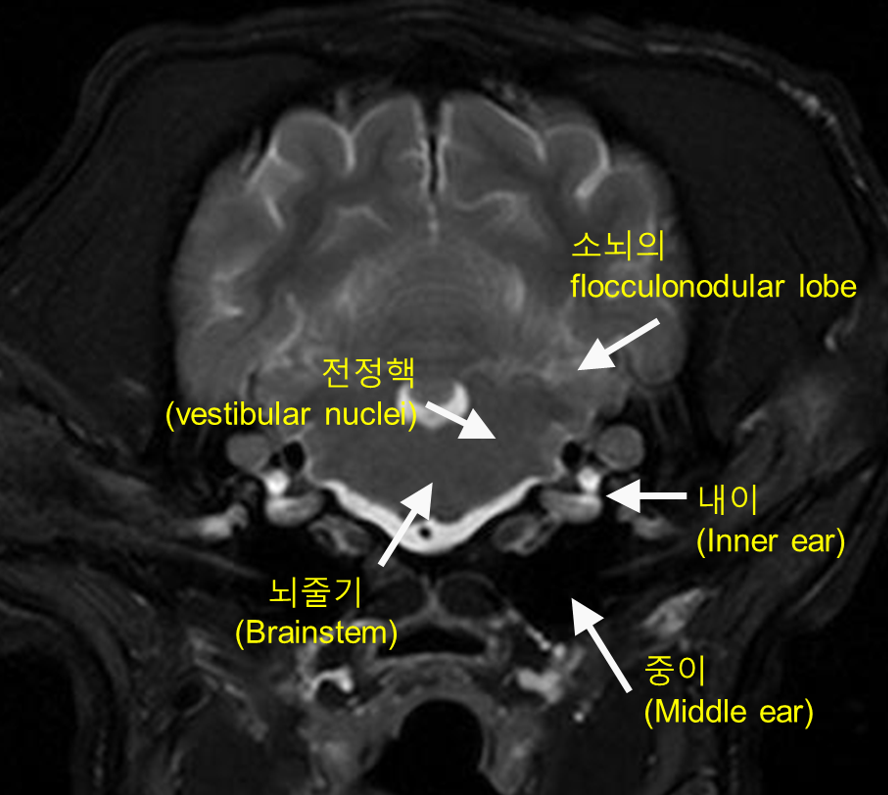

그림 2. 중추 전정계와 안면신경의 해부학

전정와우신경(CN VIII)은 연수의 등쪽가쪽(dorsolateral)에 위치한 전정핵(vestibular nucleus, 빨간색)으로 연결되며, 해당 전정핵은 소뇌의 타래결절엽(flocculonodular lobe)과 함께 중추 전정계를 구성합니다.

안면신경(CN VII)의 운동핵(파란색)은 전정핵과 해부학적으로 인접한 위치에 존재하며, 이러한 근접성은 전정 증상과 안면신경 마비가 함께 관찰될 수 있는 해부학적 근거를 제공합니다.

(출처: Comparative Veterinary Anatomy: A Clinical Approach, 2022, pp. 181–187)

전정와우신경(CN VIII)은 내이도를 통해 두개강 내로 진입한 후, 연수(medulla oblongata)의 등쪽가쪽에 위치한 전정핵(vestibular nuclei)으로 연결됩니다(그림 2).

반면 공기가 차 있는 중이(고실)는 무신호(저신호)로 나타납니다. 전정핵은 MRI 상에서 뚜렷한 경계로 구분되지는 않지만 연수(medulla oblongata)의 dorsolateral에 위치합니다.